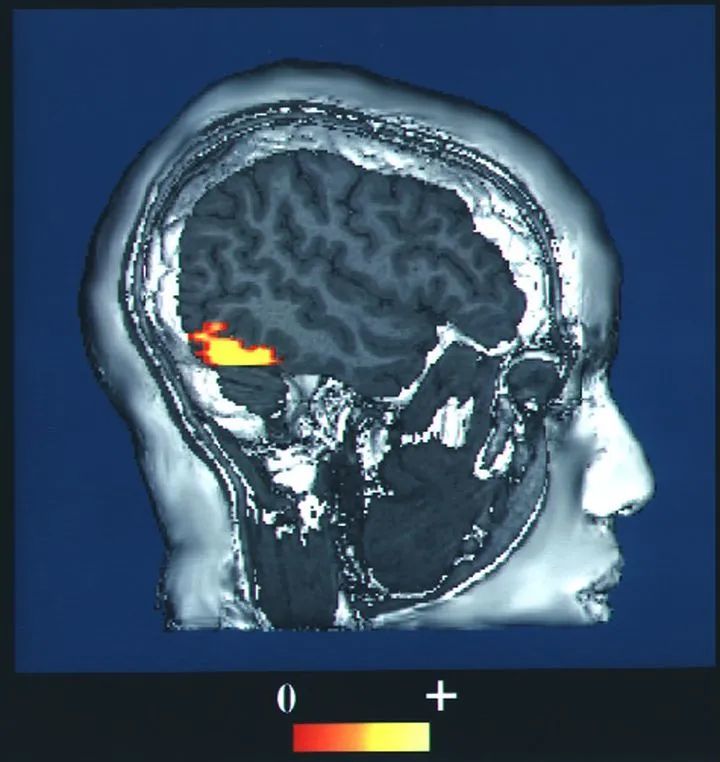

文章插图

fMRI下检测到的FFA

| 图源:Wikipedia